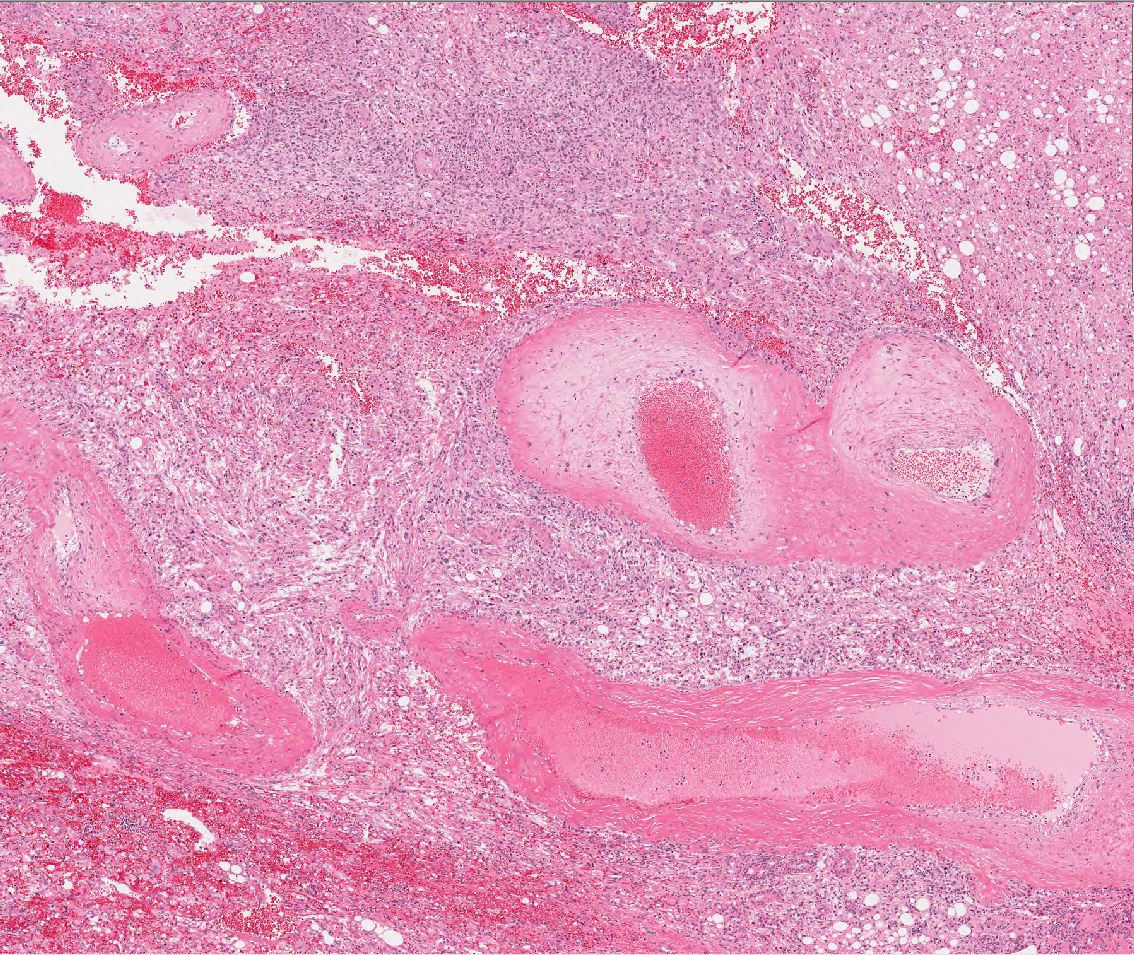

AML |

Case description (by case creator):

Atypical epithelioid angiomyolipoma with bizarre multi-nucleated giant cells